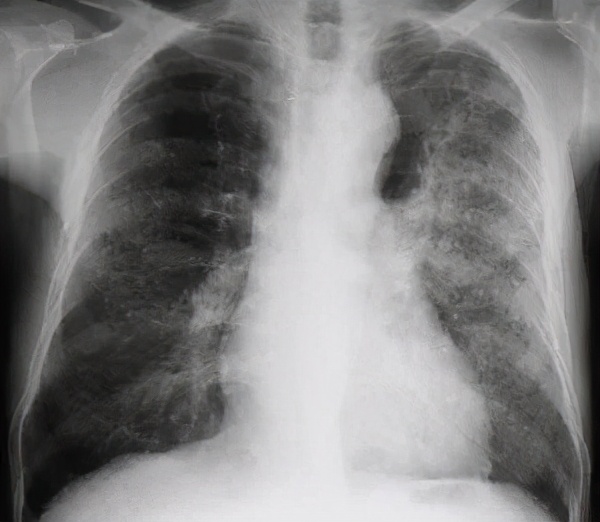

图-1:胸片示双肺可见斑片状阴影,左肺尤为明显